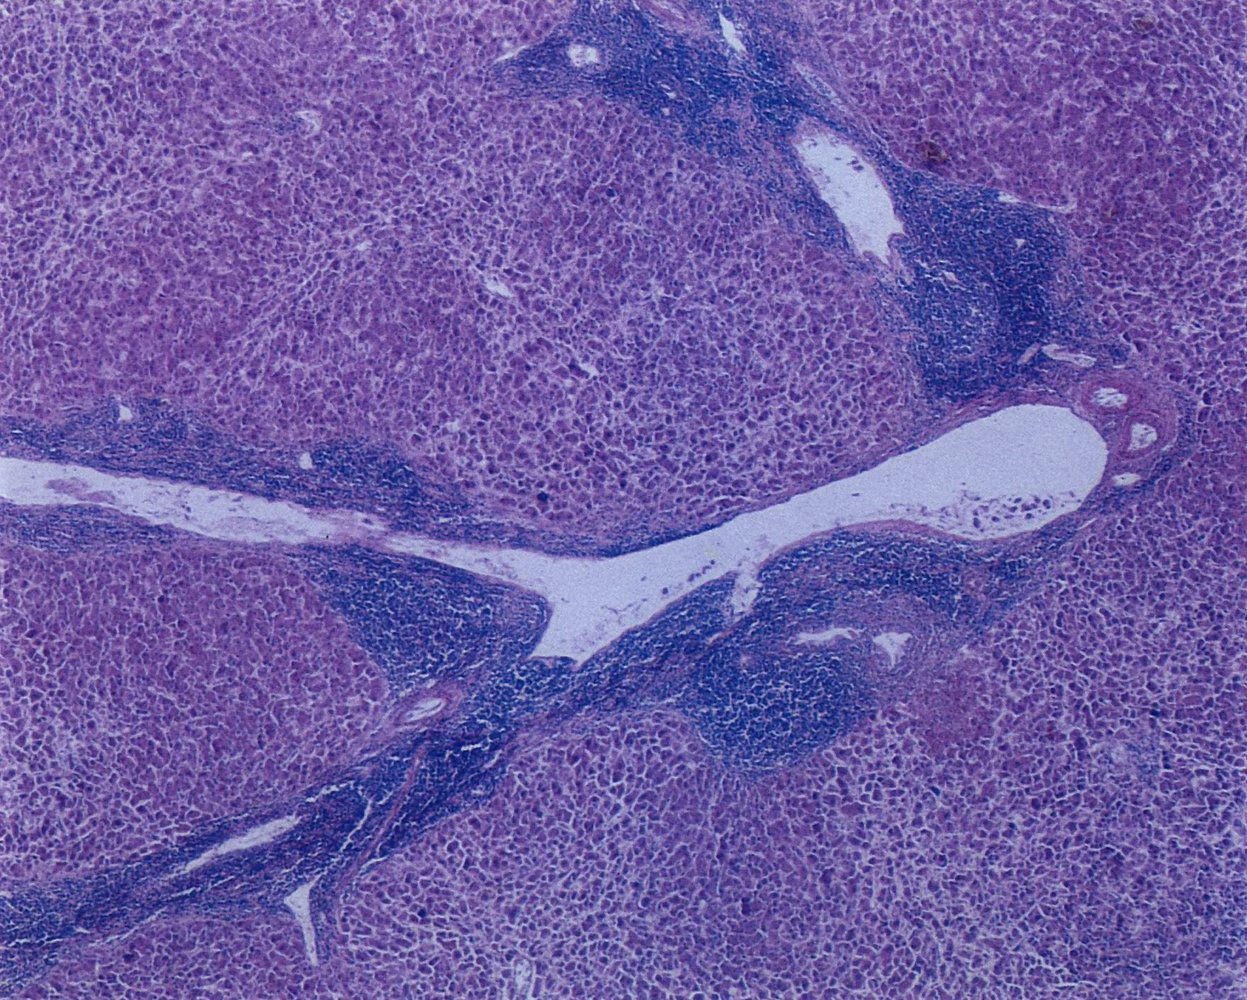

Biopsies [1]

- Lymph node biopsy: Consider if the diagnosis is uncertain or for the diagnosis of SLL or Richter transformation.